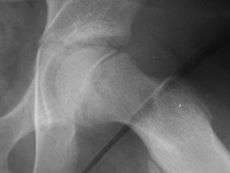

Klein's line or the line of Klein is a virtual line that can be drawn on an X-ray of an adolescent's hip parallel to the anatomically upper edge of the femoral neck. It was the first tool to aid in the early diagnosis of a slipped capital femoral epiphysis (SCFE), which if treated late or left untreated leads to crippling arthritis, leg length discrepancy and lost range of motion. It is named after the American orthopedic surgeon Armin Klein at Harvard University, who published its description and usefulness in 1952. Subsequent modification of its use has increased the sensitivity and reliability of the tool.

Klein's line is a virtual line that can be drawn on an X-ray of a child's hip parallel to the upper edge of the femoral neck. If the line does not intersect with the outermost part of the femoral head 's ball-like end, the diagnosis of a slipped capital femoral epiphysis (SCFE) is confirmed.[1]